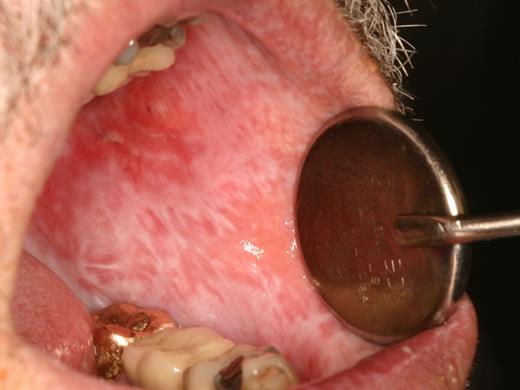

Rampant cervical dental caries affecting all of the teeth in a patient with cGVHD of the salivary glands. Demineralization changes (arrow) appear chalky white.